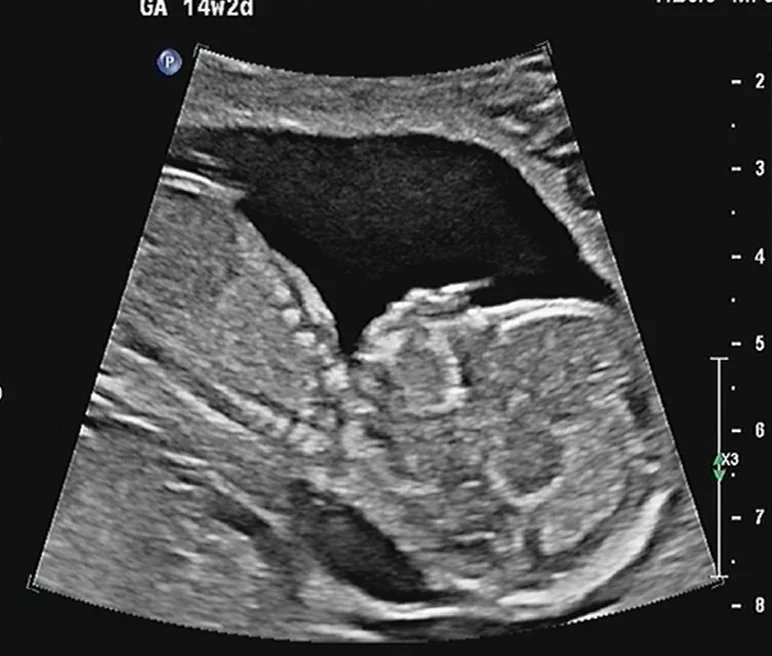

Bướu cổ thai nhi (Goiter)